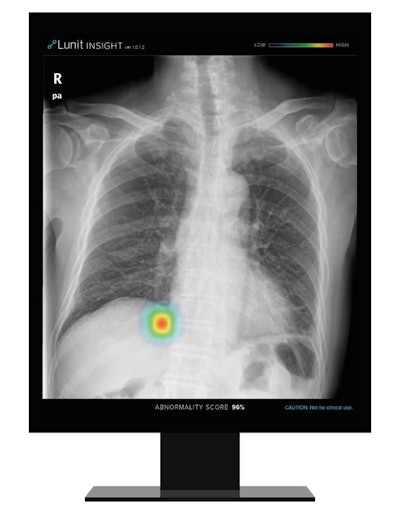

Lunit's Insight CXR algorithm. Image courtesy of Lunit.South Korea-based Lunit noted that its Insight CXR AI software is helpful for real-time detection of 10 common findings on chest x-rays and enables triage of cases to focus on those with likely abnormalities. The company said that the software's accuracy rate is high, ranging from 97% to 99%.